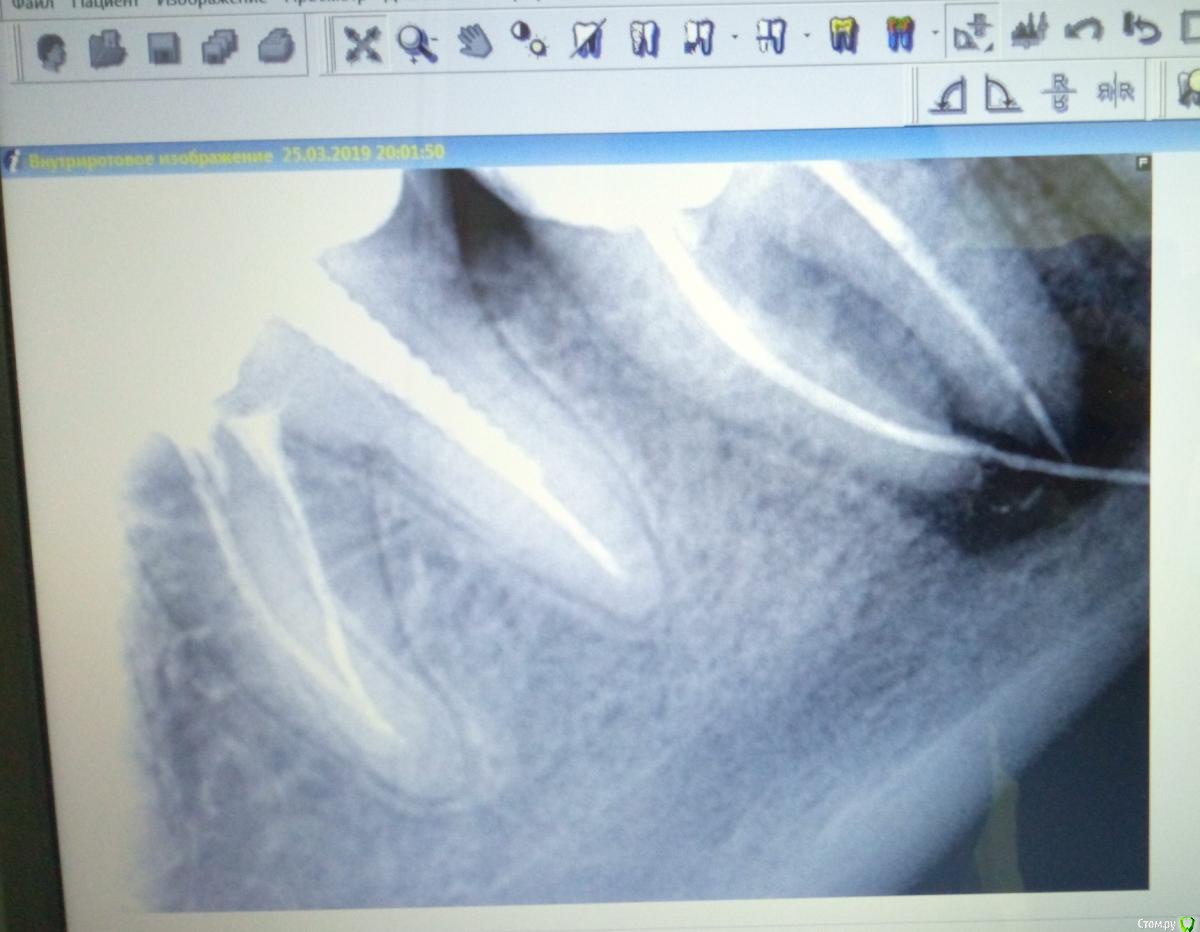

MVZ Опубликовано 25 марта, 2019 Поделиться Опубликовано 25 марта, 2019 37ой зуб. Лечили пол года назад. Был глубокий скол зуба, врач решил удалить нервы, хотя он и не болел. Проделал он всю операцию успешно, запломбировал, сделал снимок и остался доволен результатом. Через месяц начал зуб болеть при касании все сильней и сильней, так что аж челюсть заболела. Пришла к тому же врачу, он рассказал мне сказку, что это зуб мудрости проснулся и толкается, надо попить антибиотик, и на пятый день пойти к другому врачу на удаление зуба мудрости. Начала пить антибиотик, пришла на пятый день к другому врачу. Он сделал мне КТ и сказал: понятия не имею, при чем здесь зуб мудрости, к тому же он очень сложный, от его удаления вся челюсть опухнет на 2 недели, а зуб болит скорее всего из-за реакции на пломбу и типа сам пройдет, на КТ с ним всё нормально. Ну и немного мне подкорректировал пломбу на этом 37 зубе. На всякий случай. На следующий день стало легче, перестала болеть челюсть. Непонятно, это из-за антибиотиков или из-за корректировки пломбы. но боль при касании зуба не прошла. И ждала я значит, ждала, когда он пройдет. А он не прошел. Боль просто стала терпимой. А вот неделю назад вылез свищ под зубом. Пришла я к третьему доктору. Она сделала снимок, посмотрела и сказала, что понятия не имеет что это такое и что она туда не полезет! Возвращайся, говорит, к первому доктору, пусть он и разбирается по гарантии. Но как-то никакого доверия нет к тому доктору после такого Подскажете может чего-нибудь по снимку? Большое воспаление, мне сказали. А что за белые полосы в продолжение канала?? Ссылка на комментарий

suballex Опубликовано 25 марта, 2019 Поделиться Опубликовано 25 марта, 2019 Чертовщина называется гуттаперчевым штифтом. Ссылка на комментарий

krokomot Опубликовано 25 марта, 2019 Поделиться Опубликовано 25 марта, 2019 Фаил кт конечно объемный, но по результатам могу сказать, в этом зубе 3.7, запломбированы только 2 канала из 3-х, и в медиально-щечном канале выведена гуттаперча за апекс на 8 мм, что делать?, попытаться удалить гуттаперчу через канал, требуется опытный эндодонтист. Если не выйдет, удаление зуба. Боли врядли прекратятся. А удалить гуттаперчивый штифт хирургически никто не возьмется в виду близость нижнеальвеолярного нерва. 1 Ссылка на комментарий